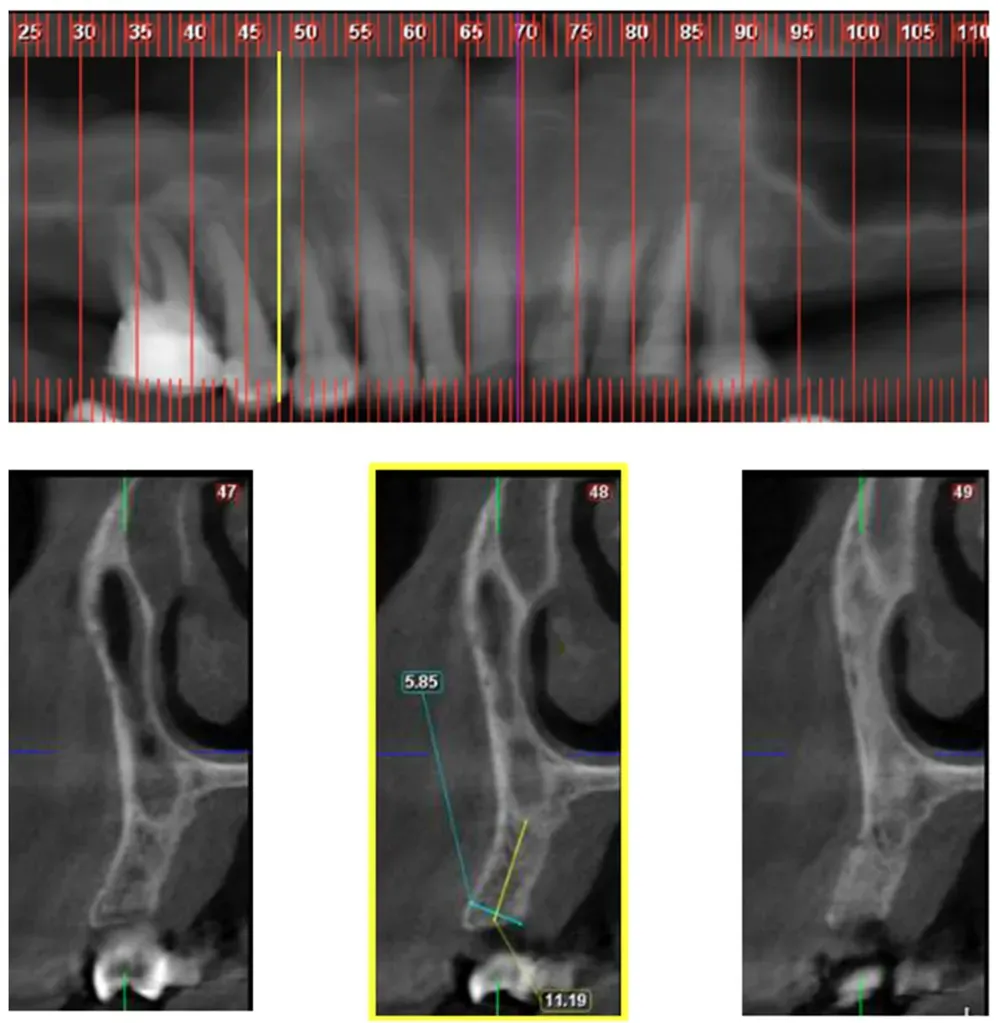

Yahya e collaboratori hanno sviluppato un sistema di classificazione che divide questa variante in classi orizzontali mesio-distali e divisioni verticali. Ma ciò che sorprende di più in questo interessante articolo è la frequenza relativamente alta della variante riscontrata dagli autori. (https://doi.org/10.3390/jcm10194293)

Nella Classe 1, il confine tra la cavità nasale e l’antro mascellare si trova sopra la parte distale del canino. In base ai dati raccolti in questo studio, si trova nel 17.2% dei casi.

Classe 1: la sezione numero 26, in giallo, delimita il confine distale della cavità nasale e si trova sopra la parte distale del canino. Da Yahya et al. (2021). Licenza CC4.0.

La Classe 2, dove il confine naso-sinusale si trova tra il margine distale del canino e quello del secondo premolare, appare nel 66% dei casi esaminati. La Classe 3, con il confine distale al margine mesiale del primo molare, si manifesta nel 16,8% dei pazienti.